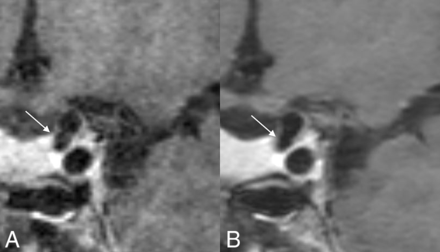

Coronal MPR postcontrast images of the clinical (A) and DLBIR (B) sequence show a medially projecting left ICA aneurysm (arrows). Note that the aneurysm wall is better depicted in the DLBIR image (B).

The current work shows that DLBIR images may not only help improve image quality but can provide considerable time savings, allowing easier and widespread implementation in routine clinical practice. The reduced image noise and consequently improved image quality can potentially improve reader confidence in image interpretation. The savings in gradient times provide further room for adding additional tissue-weightings such as T2WI TOF-MRA, while maintaining overall scan times. Even though we evaluated only a limited number of patients with intracranial lesions, these cases included a diverse array of pathologies, including atherosclerotic disease, cerebral amyloid angiopathy–related inflammation, aneurysm, basilar fenestration, and developmental venous anomaly. In all cases, lesion depiction was similar or better on the DLBIR images. For example, the DLBIR images better depicted the aneurysm wall despite proximity to the cavernous sinus (Fig 2). Similarly, visualization of atherosclerotic disease in the distal ACA was again better with the DLBIR sequence, as was the wall calcification in the V4 segment of the vertebral artery (Fig 3). Finally, the basilar artery fenestration in another patient (Fig 5) could be visualized on the DLBIR images, despite near-complete obscuration on the T1 SPACE images secondary to image noise. In the patient who eventually went on to have a brain biopsy and was shown to have cerebral amyloid angiopathy–related inflammation (Fig 4), the DLBIR images had better image quality despite visualization of the pathology on both sequences.